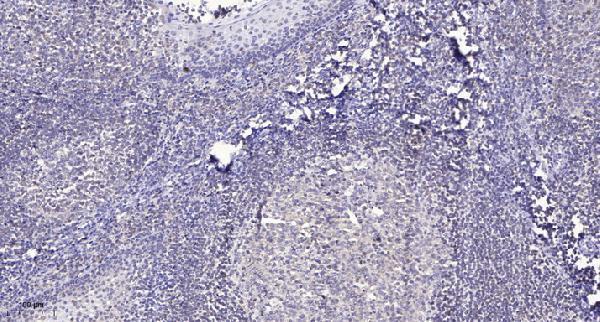

| Gene Name: | EDEM2 |

Expressed ubiquitously in all tissues tested with slightly higher levels detected in small intestine and peripheral blood leukocytes and weakest levels in brain and skeletal muscle.